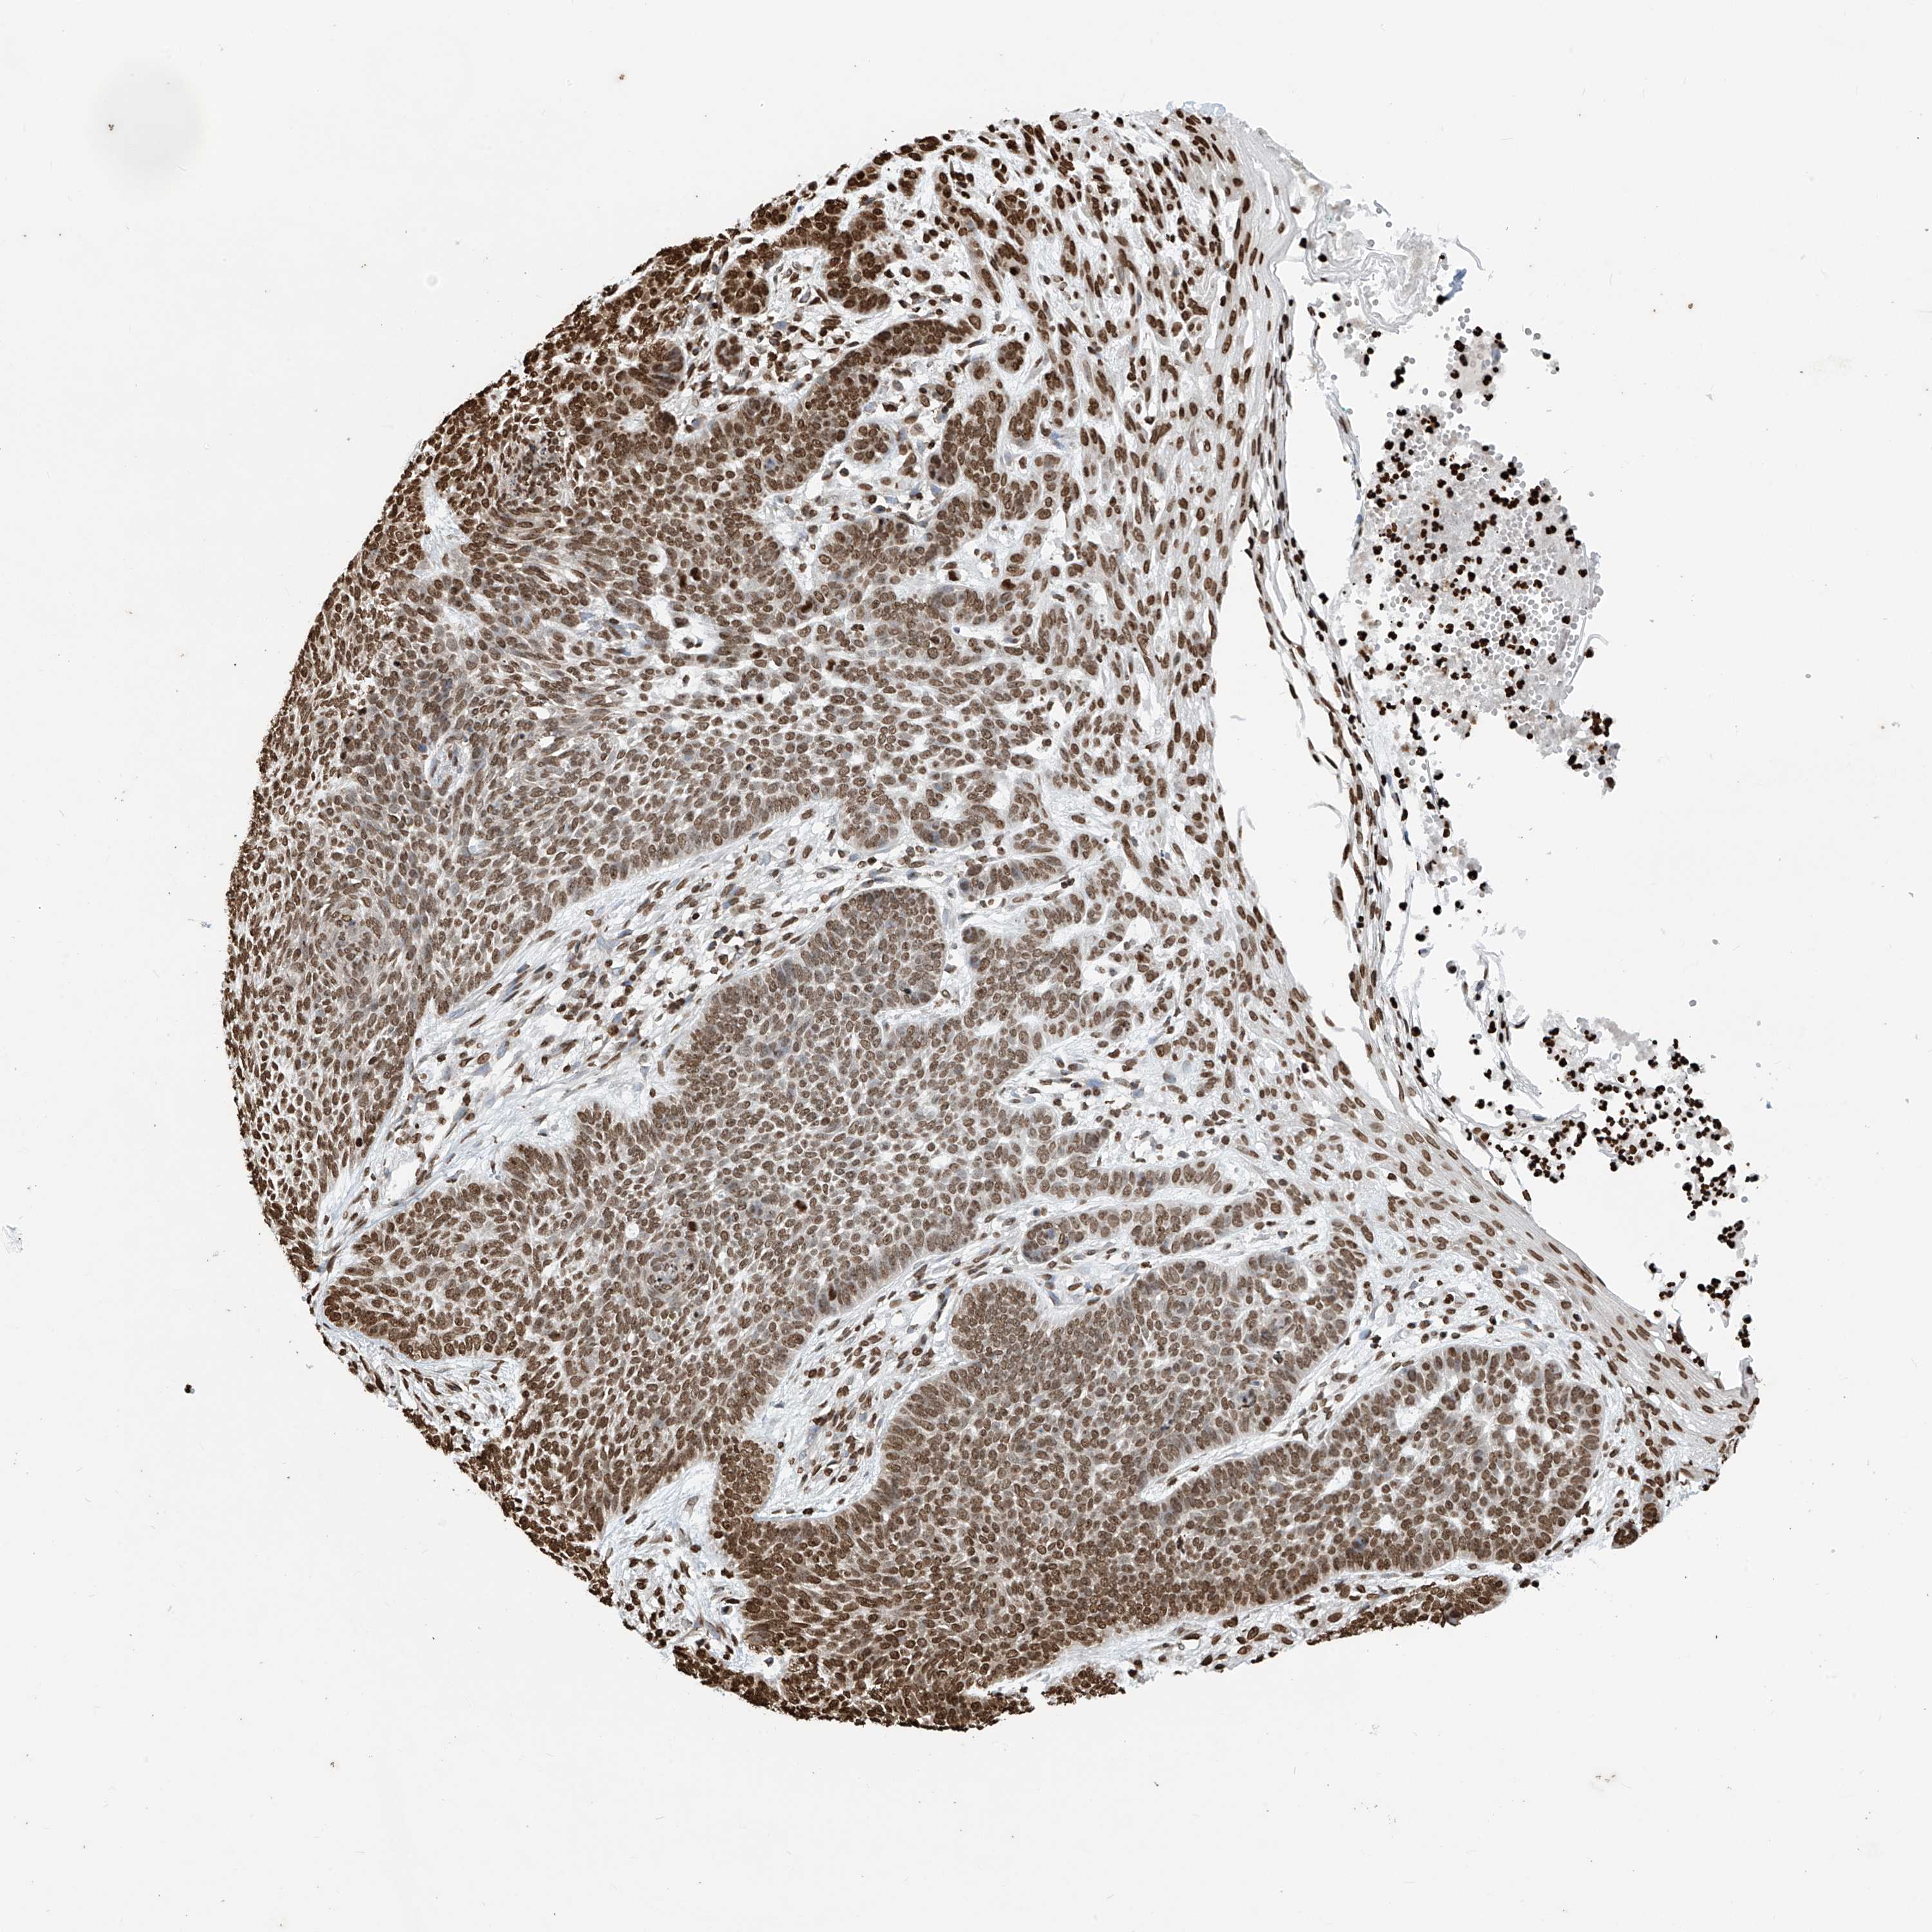

SKIN CANCER - Protein expressioni

A mouse-over function shows sample information and annotation data. Click on an image to view it in a full screen mode. Samples can be filtered based on level of antibody staining by selecting one or several of the following categories: high, medium, low and not detected. The assay and annotation is described here.

Antibody stainingi

Antibody staining in the annotated cell types in the current human tissue is reported as not detected, low, medium, or high, based on conventional immunohistochemistry profiling in selected tissues. This score is based on the combination of the staining intensity and fraction of stained cells.

Each image is clickable and will lead to virtual microscopy that enables deeper exploration of all samples and also displays staining intensity scores, fraction scores and subcellular localization as well as patient and tissue information for each sample.

Antibody HPA036134

Staining

High

Intensity

Strong

Quantity

>75%

Location

Nuclear

Squamous cell carcinoma, NOS